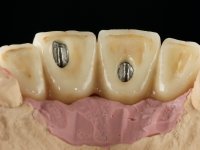

Primeira Fase

Foram feitas as extrações das raízes dos dentes 2.1 e 2.2 porque estavam a incomodar. Após 3 meses de cicatrização fez-se o exame imagiológico e estudo implantar para colocação do implante no local do 2.1.Foi colocado um implante de 4.1mm de diâmetro por 10mm de altura, colocado ao nível ósseo. Passados 2 meses após a cirurgia implantar, foi feita a segunda cirurgia para colocação de um parafuso de cicatrização. Foi feita a impressão ao implante com técnica de moldeira aberta com silicone de dupla viscosidade um mês após. No laboratório foi confecionada uma infraestrutura metálica para uma ponte de 2 elementos aparafusada ao implante. Esta infraestrutura apresentava 2 apoios palatinos para ajudar a estabilizar os dentes 1.1 e 2.3 a recuperar do traumatismo. Recuperados os dentes, os apoios poderiam ser retirados. Esta peça apresentava uma conexão interna ao implante com sistema anti-rotacional. A prova da infraestrutura foi feita em boca sendo o seu correto ajuste verificado com controle imagiológico. No revestimento da infraestrutura foi utilizada cerâmica de tonalidade coronária e gengival. Depois de verificada em boca e aprovada pelo paciente a ponte foi apertada definitivamente e o orifício de acesso obturado.